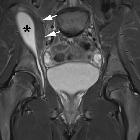

Subperiosteal

hematoma of the ilium: an unusual complication of acetabular fracture. A large subperiosteal hematoma of the iliac bone (asterisk) appears as a hyperintense, lens-shaped lesion delimited between the internal aspect of the right iliac bone and the right iliacus muscle (arrows), which is shifted medially.